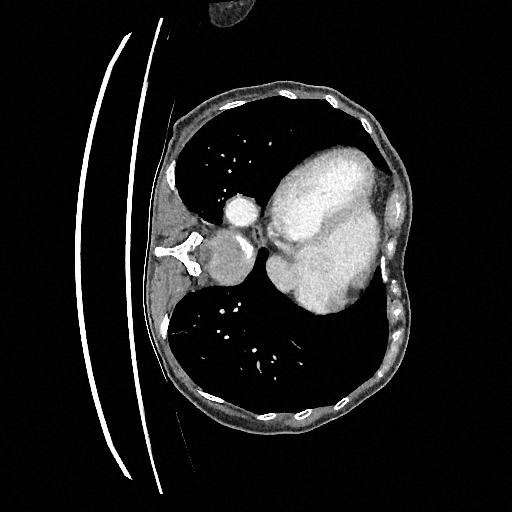

Sampling results

Original

Perturbed

Samples

Sampled